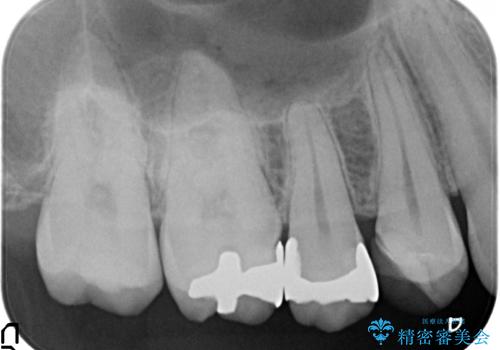

X線写真より不適合な銀歯が確認できました。

銀歯・虫歯を丁寧に除去し、残存歯質にピッタリと合ったセラミック修復を計画します。

修復物は歯にピッタリと精密な形で形成。印象をする必要があります。

精度が悪いと今回の銀歯のように不適合な状態で装着されてしまいのちのちしみたり、虫歯の原因となることもしばしばです。